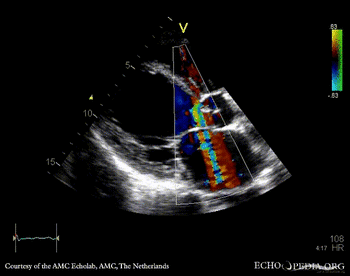

E00804.gif E00805.gif

PLAX with Color Doppler: severe aortic regurgitation A4CH: dilated atria and ventricles, poor function of left ventricle